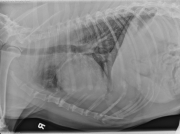

L LAT Thorax

There is a diffuse bronchointerstitial pattern throughout the lungs. The bronchial walls are asymmetrically thickened and visible well out into the periphery. The bronchi do not taper well which may indicate bronchiectasis. Multiple lobar bronchi are visualized with thickened walls. The end-on bronchi form donuts, or cygnet rings. There is also a focus of increased interstitial pattern at the tip of the bronchus to the right cranial lung lobe. The cardiovascular structures are within normal limits.

• Bronchointerstitial pattern – eosinophilic bronchopneumonia (PIE), parasitic pneumonia, less likely neoplasia.

• Interstitial pattern right cranial lobe – focal pneumonia or fibrosis

• Poorly tapering bronchi – possible bronchiectasis

The bronchoscopic exam revealed copious amounts of mucus within the airways. A bronchioalveolar lavage showed increased numbers of eosinophils and neutrophils supporting a diagnosis of eosinophilic bronchopneumopathy. No organisms were cultured from the BAL.¹